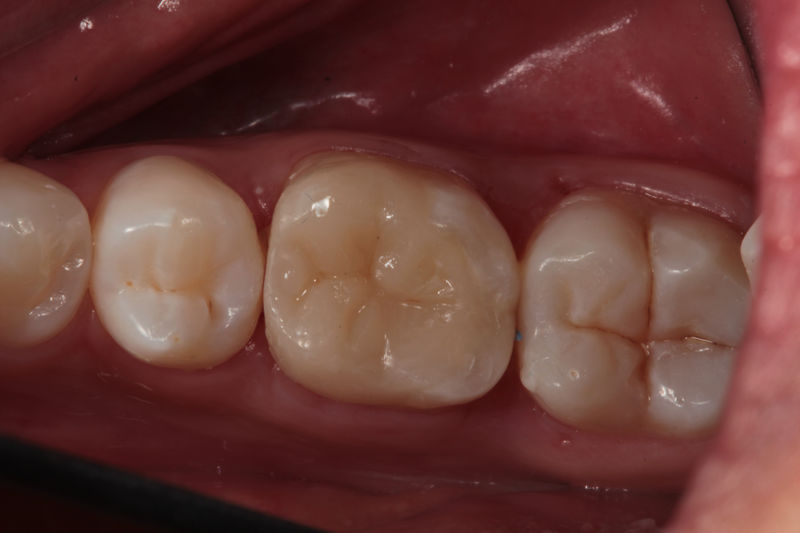

Restauraciones fabricadas en el laboratorio con materiales estéticos, los cuales cubren de manera parcial dientes posteriores. Se utilizan primariamente para restaurar dientes con caries, fracturas y/o defectos amplios. Para poder enviar el caso al laboratorio se toman impresiones utilizando materiales de impresión o técnicas modernas digitales.

Restauraciones fabricadas en el laboratorio con materiales estéticos, los cuales cubren de manera total dientes anteriores y posteriores. Se utilizan primariamente para restaurar dientes con caries, fracturas y/o defectos amplios, así como soportes de puentes. Para poder enviar el caso al laboratorio se toman impresiones utilizando materiales de impresión o técnicas modernas digitales.